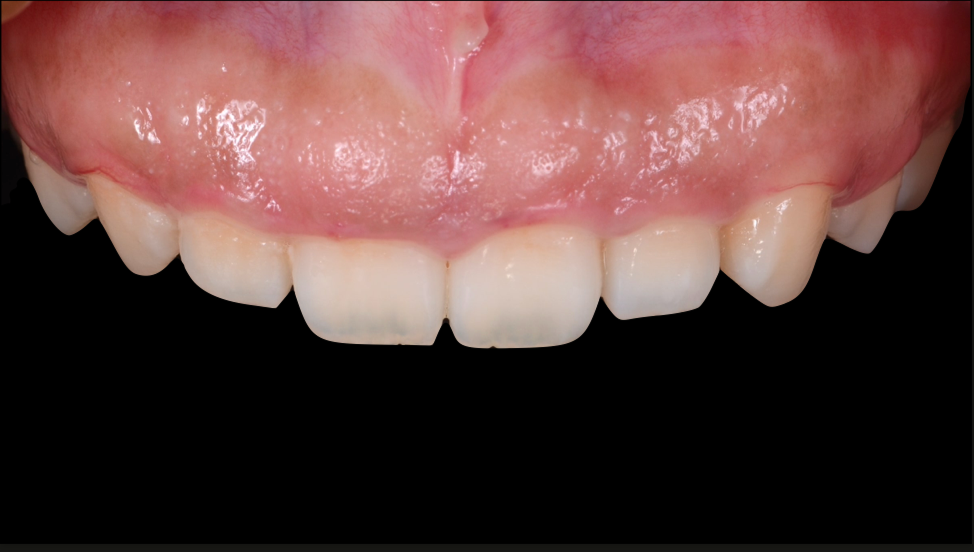

ガミースマイルを歯周形成外科で改善した症例

- 年代、性別 27歳・女性

- 来院動機 ガミースマイルを治したい

- 治療内容 歯周形成外科